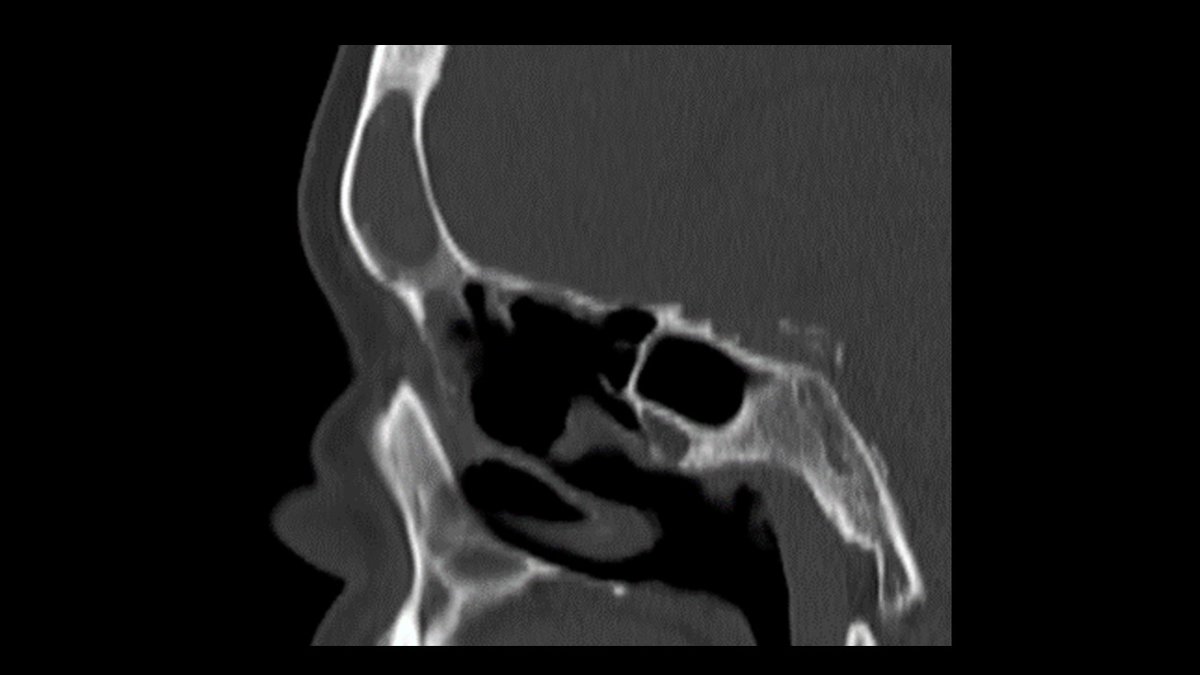

Just sharing the link to my case submission on MACS that is now available on the Cushing’s Hub website as an interactive case study. cushingshub.com/case-studies/a… @springermeded #Endotwitter